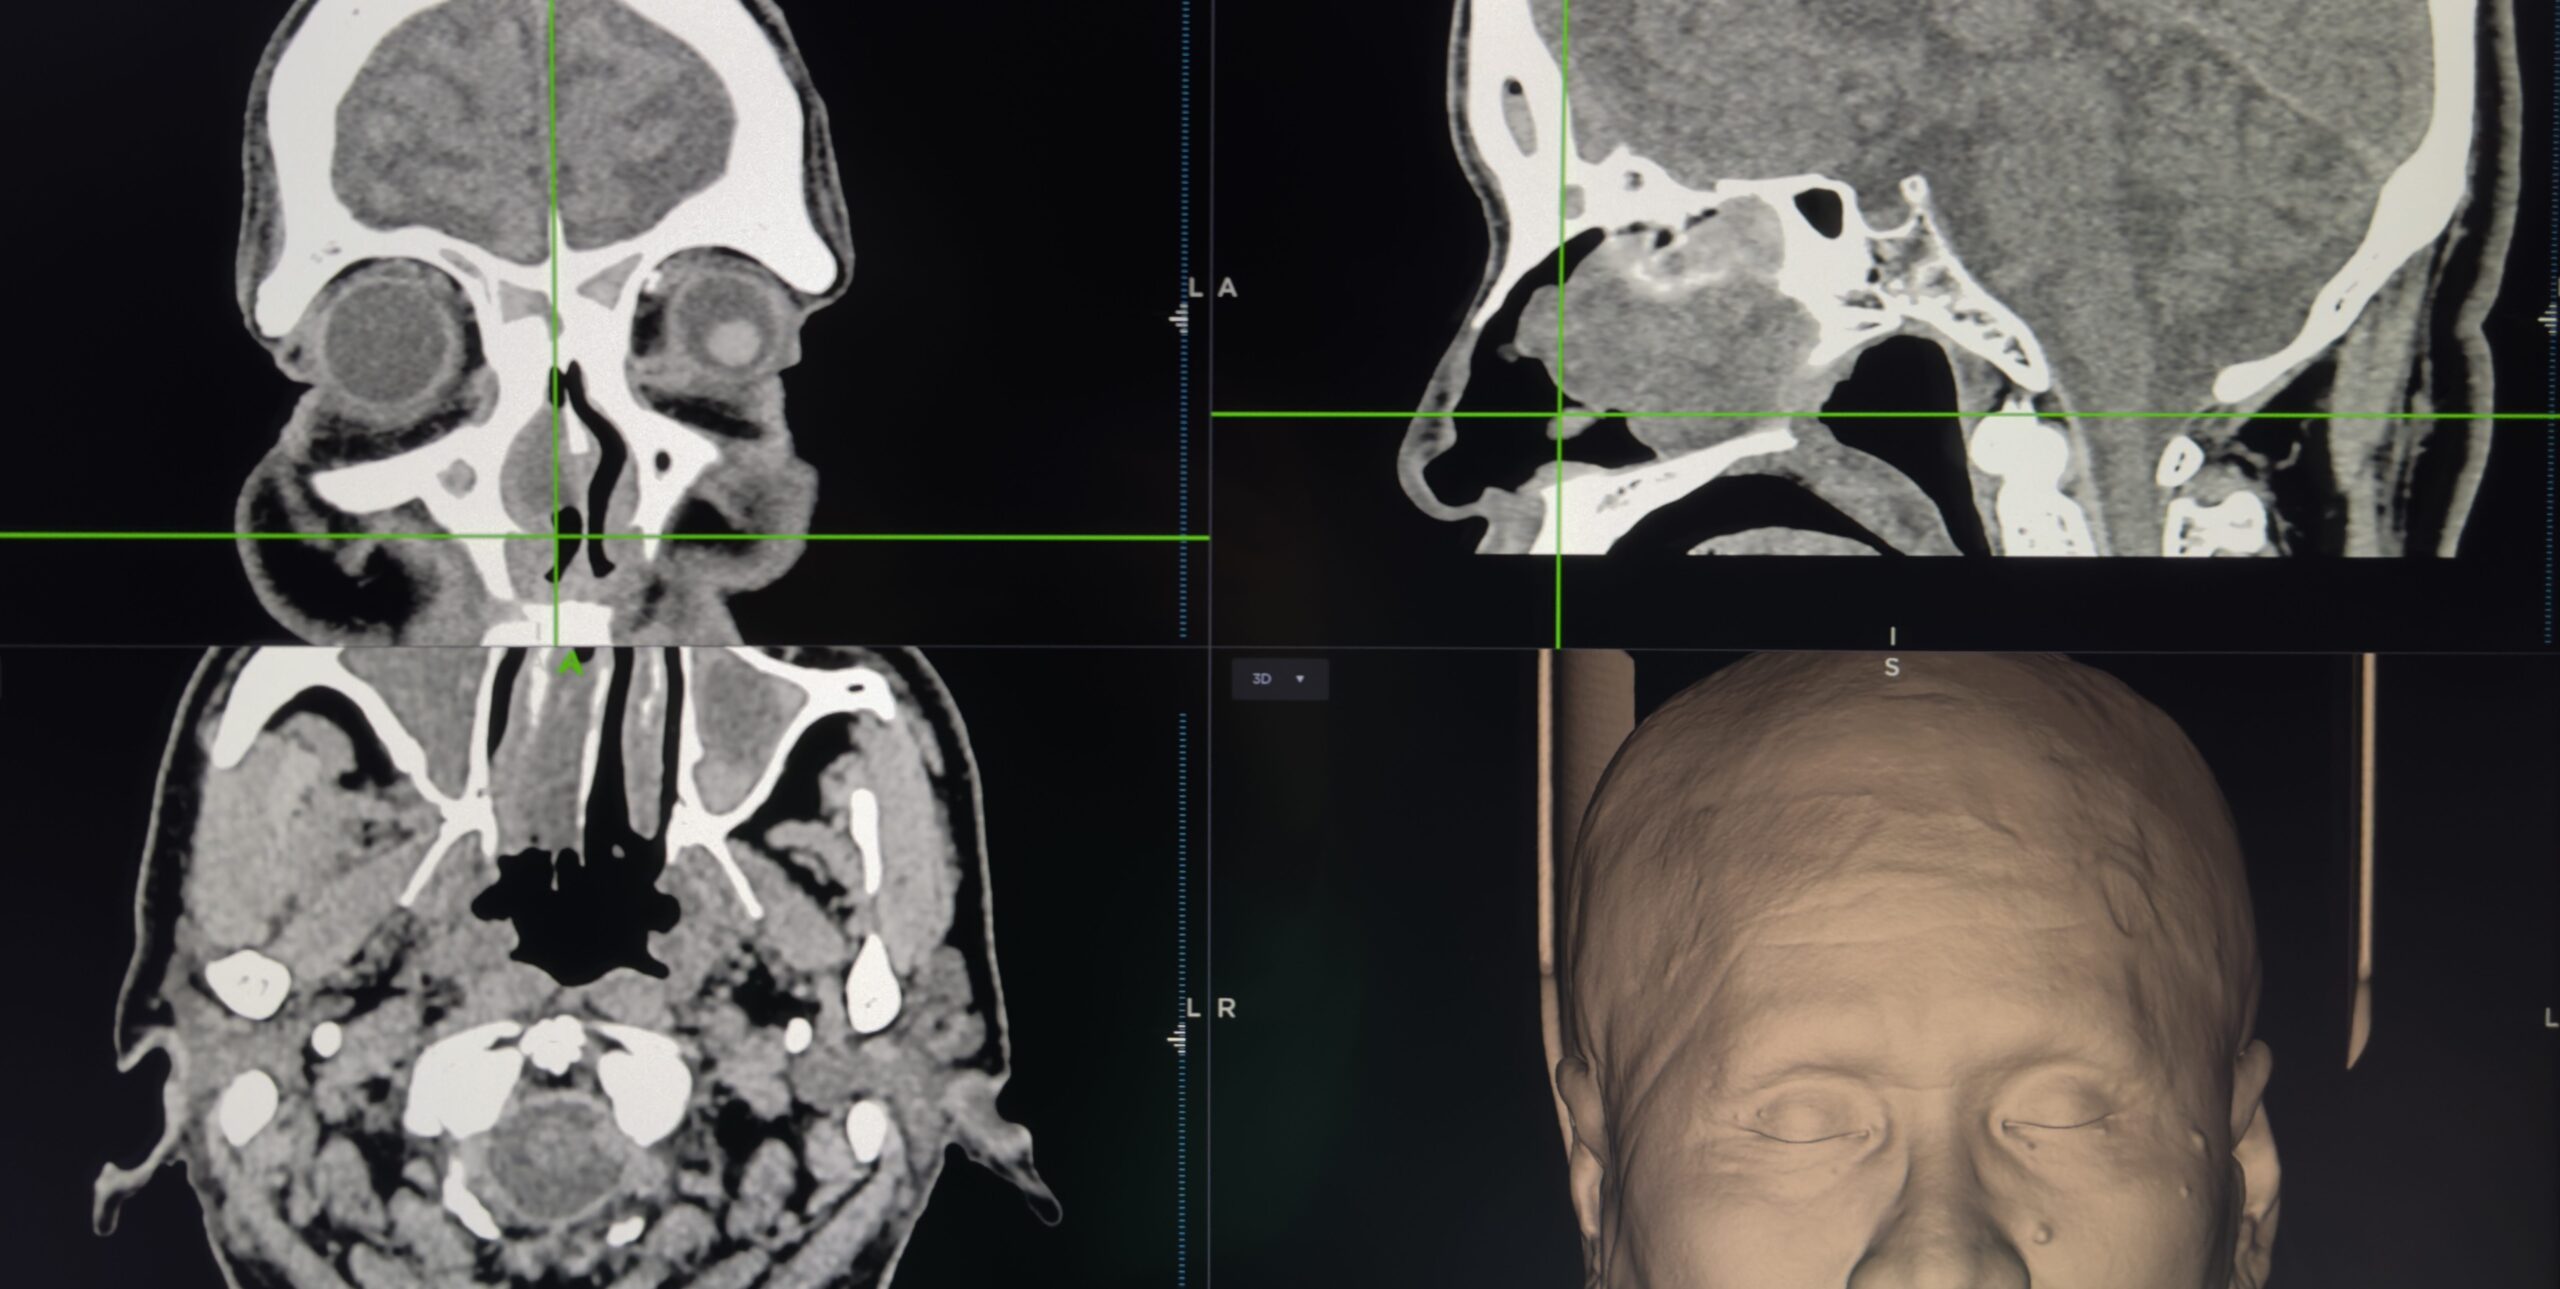

臺北市立聯合醫院忠孝院區耳鼻喉科主任朱峻緯表示,3D立體定位導航手術是利用GPS相似的運作概念來輔助醫師執行手術,藉由將病人術前電腦斷層(CT)或磁振造影(MRI)的影像輸入導航系統,藉由電腦掌握手術器械與開刀處的相對位置,能有效指引病灶在解剖構造的區域,隨時檢查開刀位置與情況,就如同開車時有汽車導航衛星定位ㄧ般,能在內視鏡鼻竇手術中提供即時且精準定位,讓手術更安全、更放心。